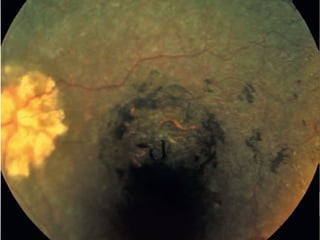

• Triad of

• bone-spicule retinal pigmentation

• arteriolar attenuation

• ‘waxy’ disc pallor

Progression

• Bilateral mid-peripheral intraretinal perivascular

‘bone-spicule’ pigmentary changes with

arteriolar narrowing

• Then a gradual increase in density of the

pigment

• Anterior and posterior spread

• Peripheral pigmentation may become severe,

with marked arteriolar narrowing and disc pallor

• The macula may show

• Atrophy

• epiretinal membrane formation

• cystoid macular oedema (CMO)

• Myopia is common.

• Optic disc drusen occur more frequently